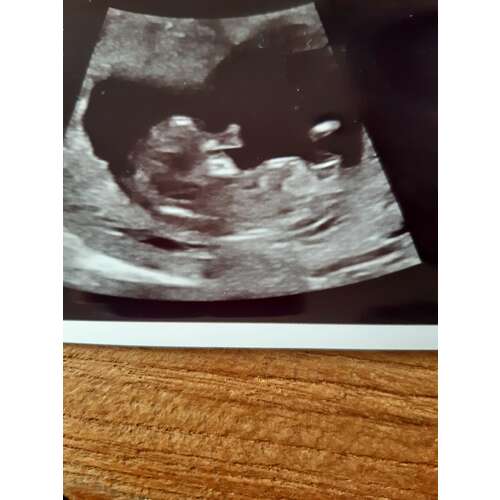

Deze heb ik nog

Zover ik kan zien denk ik 💗